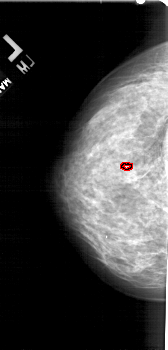

A_1755_1.RIGHT_MLO

RIGHT_MLO LINES 5491 PIXELS_PER_LINE 2626 BITS_PER_PIXEL 12 RESOLUTION 43.5 NON_OVERLAY

FILE: A_1755_1.LEFT_MLO.OVERLAY

TOTAL_ABNORMALITIES 1

ABNORMALITY 1

LESION_TYPE CALCIFICATION TYPE PLEOMORPHIC DISTRIBUTION CLUSTERED

ASSESSMENT 4

SUBTLETY 1

PATHOLOGY BENIGN

TOTAL_OUTLINES 1

BOUNDARY